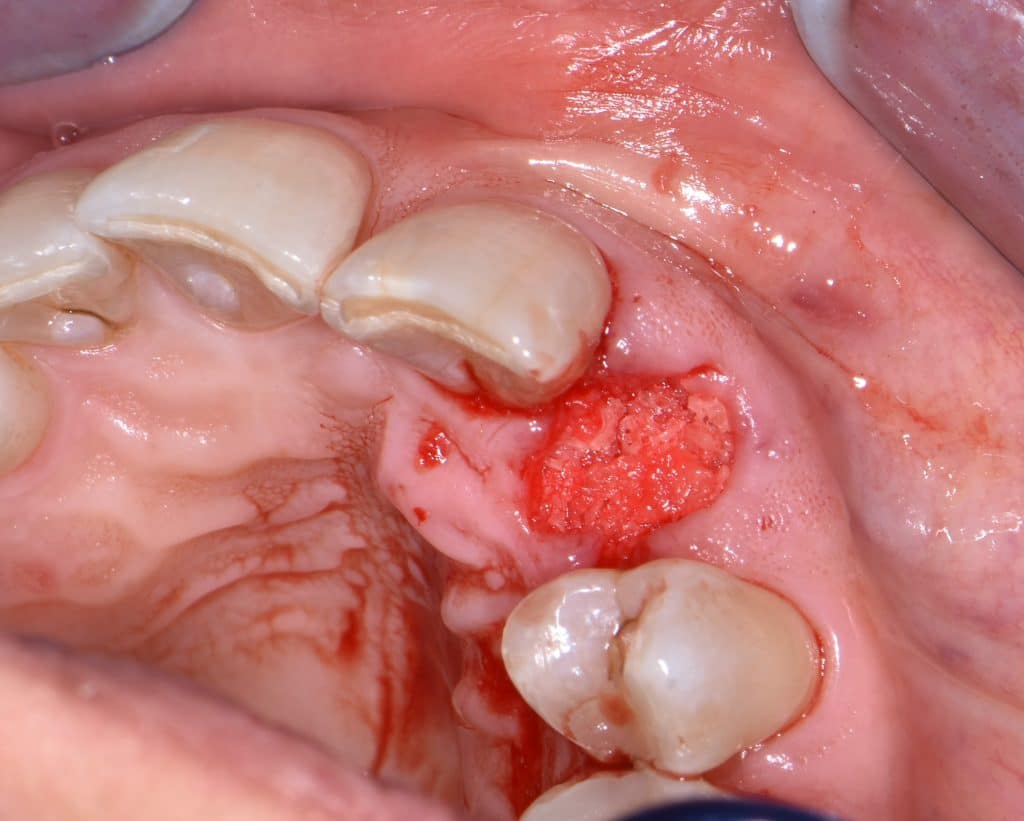

La pz N.G. di anni 52 (ASA 1) viene visitata nel mese di settembre 2017 per la mobilità ed inestetismo dell’elemento protesico 22, (foto iniziali sequenza 1) si evidenzia una frattura parziale della radice, si decide per l’estrazione ( foto sequenza 2) e sostituzione dell’elemento con un restauro implanto-protesico. Purtroppo la scarsa quota ossea apicale all’alveolo post-estrattivo (foto 2 rx) e l’alta valenza estetica dell’elemento ci rende cauti e si programma una socket preservation post estrattiva con l’ausilio delle membrane di prf (foto prf e socket sequenza 3 e 4). Durente i 5 mesi di guarigione la pz porta una protesi parziale mobile (foto 5,2) , a guarigione del sito post estrattivo si evidenzia una buona conservazione dei volumi osseo-gengivali,(foto guarigione sequenza 6) se pur presente una recessione distale all’elemnto 21.Nel mese di febbraio 2018 si procede all’inserimento di un impianto max-stability 3,75x12mm disegnando un lembo anticipato palatino per consentire un aumento dei tessuti vestibolari suturando con tecnica rool flap e trasformando l’elemento parziale mobile in una corona singola a carico immediato sul moncone temporameo applicando i concetti protesici bopt , (foto impianto moncone protesi provvisoria sequenza foto 7-8-9). Durante il periodo di maturazione dei tessuti molli vengono apportate opportune modifiche ai profili del provvisorio al fine di dare maggior spazio al tessuto gengivale, ( fotosequenza 10).Dopo circa 2 mesi dal protesizzazione provvisoria si è proceduto alla realizzazione del manufatto protesico con tecnica chair side sirona con l’ausilio del t-base (foto sequenza 11-12-13), realizzando in una sola seduta una corona in disilicato, ottenendo un risultato più che soddisfacente (Foto 14). Nel controllo a 3 mesi dal carico definitivo si apprezza la perfetta conservazione dei livelli ossei e gengivali. (foto sequenza 15).concludo con un follow up a 18 . Tengo a sottolineare che un caso come questo è stato conducibile con buoni risultati solo grazie alla piena fiducia della pz e alla sua massima motivazione e collaborazione. Ad oggi la pz sorride soddisfatta del risultato. E questo rappresenta la massima ricompensa di chi dedica tutto se stesso alla professione.